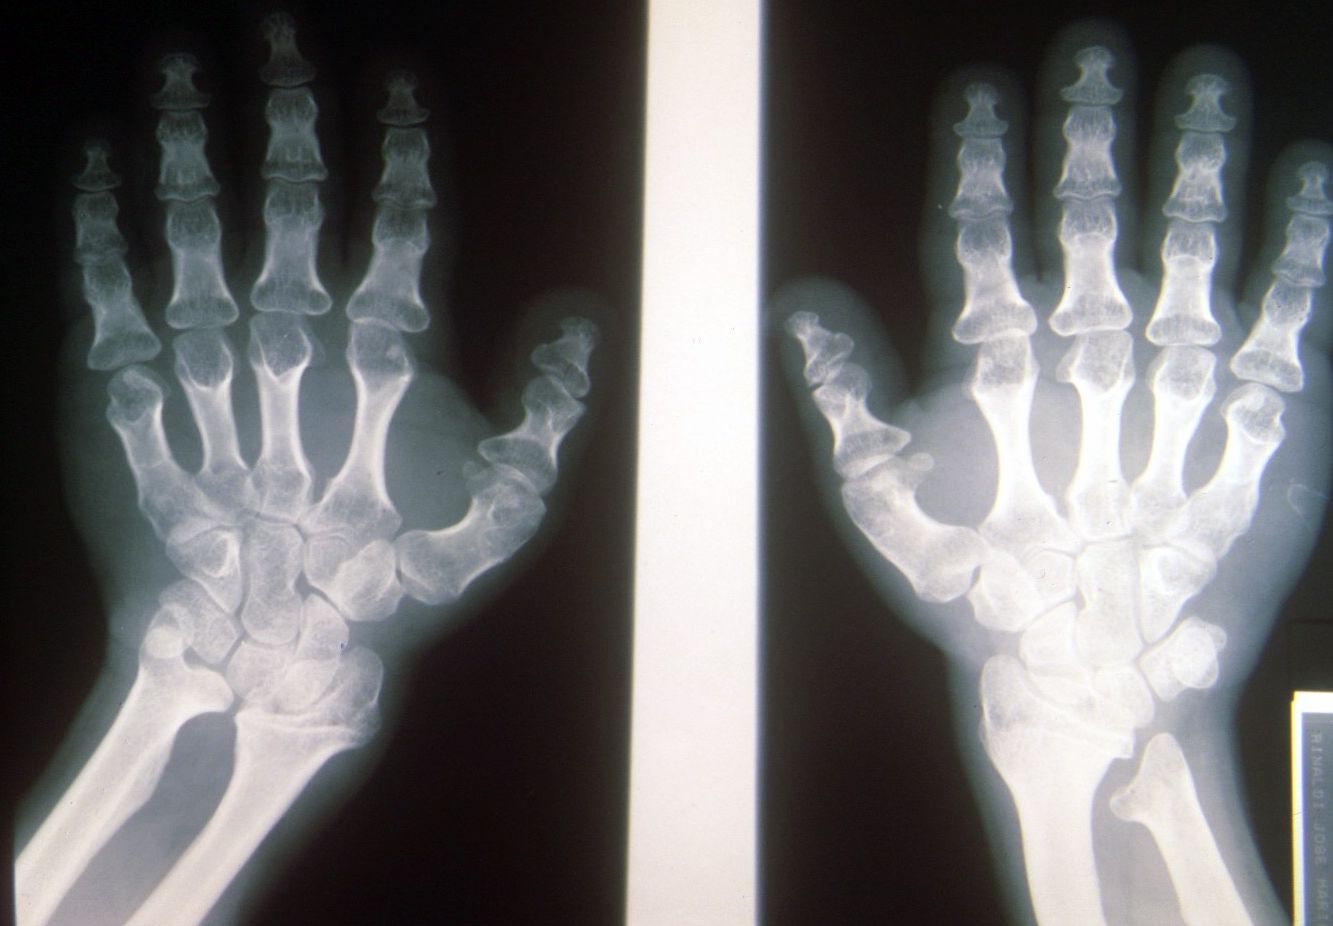

Seudoacondroplasia. [Pseudoachondroplasia]